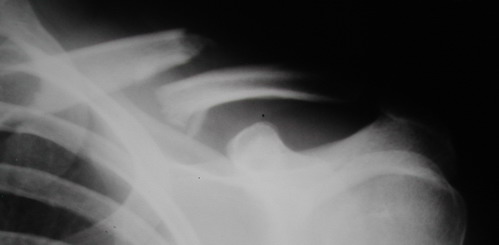

Во время стажировки в Австрии не мог не поинтересоавться, как австрийские хирурги лечат переломы ключицы. Оказалось, при переломах без смещения или с небольшим смещением накладывают восьмиобразную повязку, в остальных случаях выполняют остеосинтез пластинами.

Однако, чтобы уснуть с аппаратом внещней фиксации на ключице нужно "устать" не меньше, чем в рамке Чижина. К тому же, у некоторых больных присутсвует страх, что что-то в аппарате может раскрутиться, зацепиться за одеяло или подушку, или воспалиться. Крепко спят пациенты после качественного стабильного погружного остеосинтеза, когда ничего не торчит на коже. Особенно сладко спится после принятия душа или ванны. Это возможно после снятия швов. А вот у "чижиков" и "аппаратчиков" с полноценными водными процедурами определенные трудности.